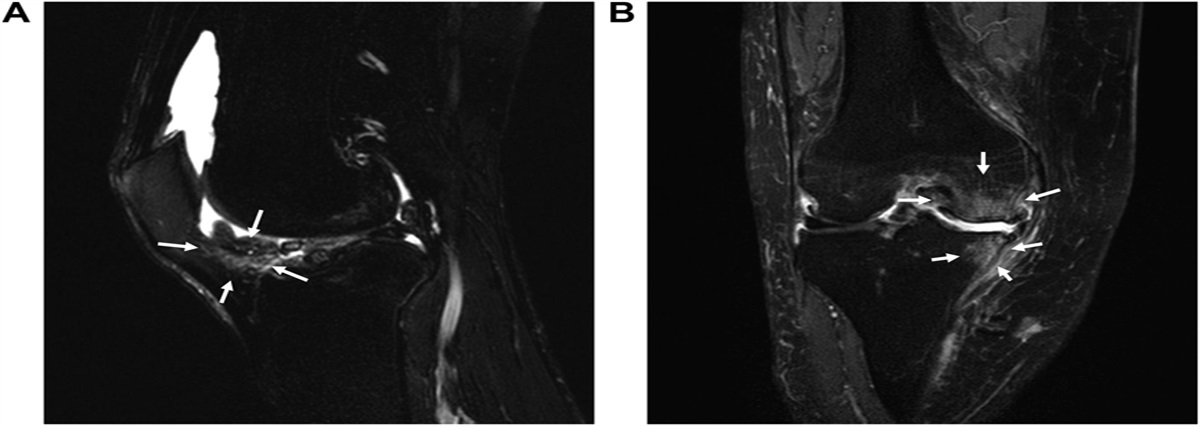

Pathology of knee osteoarthritis pain: contribution of joint structural changes and pain sensitization to movement-evoked pain in knee osteoarthritis

Introduction: Movement-evoked pain (MEP) is the primary symptom in patients with knee osteoarthri